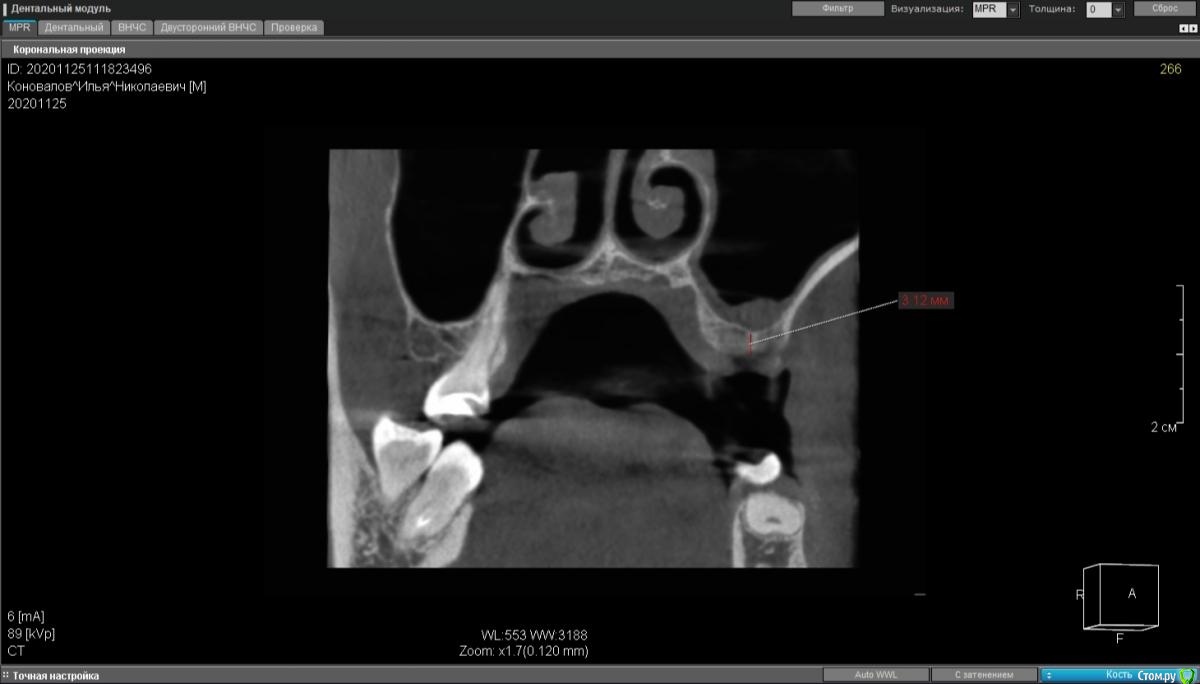

moises Опубликовано 30 ноября, 2020 Поделиться Опубликовано 30 ноября, 2020 Добрый день,коллеги.3 месяца назад удалены 25,26.Планируется установка 2х имплантатов .Если в области 15 можно было пойти с закрытым синуслифтингом, то в области 16 кости 3мм.Нужна помощь в тактике лечения.?Идти на ОСЛ в области 2х зубов и отсроченно имплантаты ? И можно ли с такой утолщенной слизистой его производить?Спасибо!P.S.Закрытые синусы делаю,открытые -делал только на фантомах и препаратах. Ссылка на комментарий

kramer Опубликовано 30 ноября, 2020 Поделиться Опубликовано 30 ноября, 2020 Проверить по кт, что там с соустьем, сделать ОСЛ с одномоментной имплантацией 1 Ссылка на комментарий